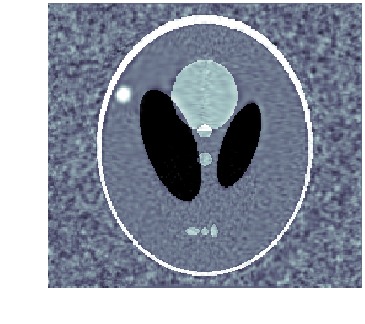

When template has correct topology and intensity levels, then \acLDDMM-based indirect registration with geometric group action is remarkably stable as shown in [9]. Using a geometric group action, however, makes it impossible to create or remove intensity, e.g., it is not possible to start out from a template with a single isolated structure and deform it to a image with two isolated structures. This severely limits the usefulness of \acLDDMM-based indirect registration, e.g., spatiotemporal images (moves) are likely to involve changes in both geometry (objects appear or disappear) and intensity. See fig. 1 for an example of how wrong intensity influences the registration.

As noted in [9], one approach is to replace the geometric group action with one that alters intensities, e.g., a mass preserving group action. Another is to keep the geometric group action, but replace \acLDDMM with a framework for diffeomorphic deformations that acts on both geometry and intensities, e.g., metamorphosis. This latter approach is the essence of metamorphosis-based indirect registration.

We clearly see that metamorphosis based indirect registration can handle a template with wrong intensities. As a comparison, see fig. 1(c) for the corresponding \acLDDMM based indirect registration using the same template and data. Furthermore, the different trajectories also provides easy visual interpretation of the influence of geometric and intensity deformations.